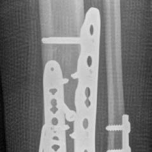

Fig 2.2-5 Intraoperative images.

1. Posterior, anterolateral, and medial plates have been applied. Anatomical reduction and stable fixation of the tibial plafond articular surface has been successfully achieved. At this stage, the fibula had not yet been fixed.

2. Lateral image shows a well-reduced tibial articular surface and a congruent tibiotalar joint.